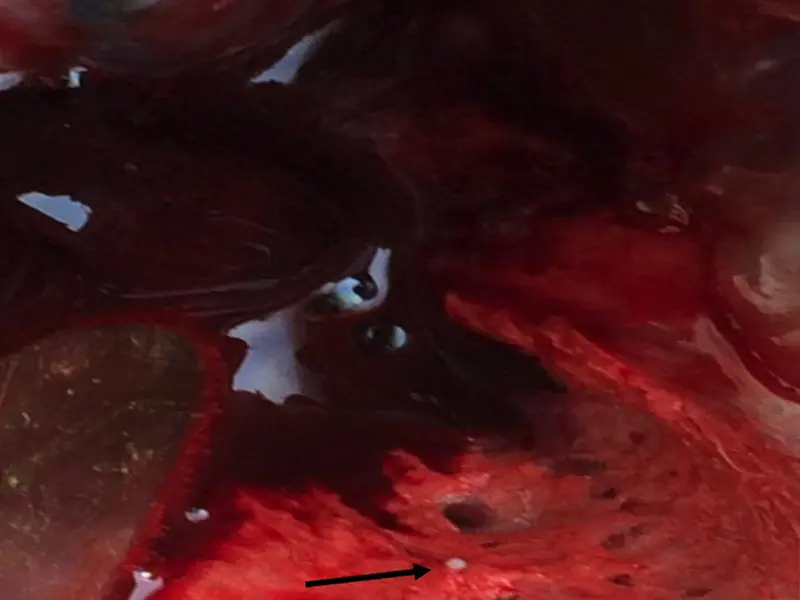

Anatomopathological examination revealed:

- single lesions on the air sacs in the form of small, white clusters – fungal nodules (Fig. 1)

- single fungal nodules in the lungs (Fig. 2 and 3)

Fig. 1 Fungal nodules on air sacs

Fig. 2 Fungal nodules in the lungs

Fig. 3 Fungal nodules in the lungs